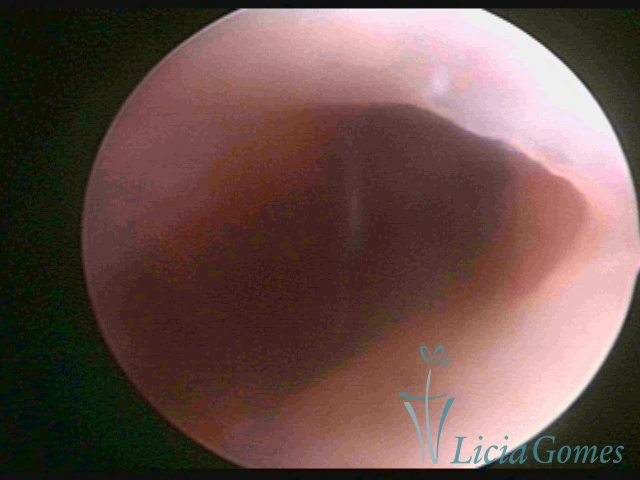

Terceira porção ou porção superior

Apresenta a mucosa com a superfície lisa e pouco vascularizada até a altura do orifício interno